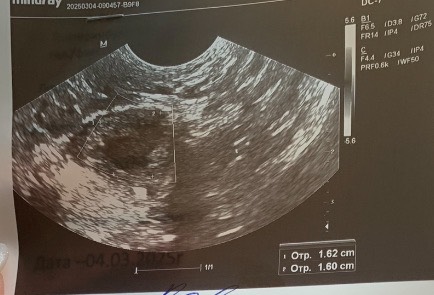

По результатам узи есть желтое тело, но свободная жидкость в тазу не лоцируется, это вообще нормально? Так может быть?

И при этом на узи он выглядит как желтое тело, но жидкости позади матки нет. Вот о чем я, поэтому лютеинизация и происходит, а овуляция нет

@katefromtheswamp обязательно должна быть жидкость позади матки хотя бы совсем совсем в незначительном количестве, высокий прогестерон и четкий хороший кольцевой кровоток у ЖТ, тогда можно быть уверенным что овуляция была.

@katefromtheswamp как бабочка он выглядит, как цветочек, посмотрите реальные фото узи жт у него неровные края и чаще всего сетчатая структура на узи